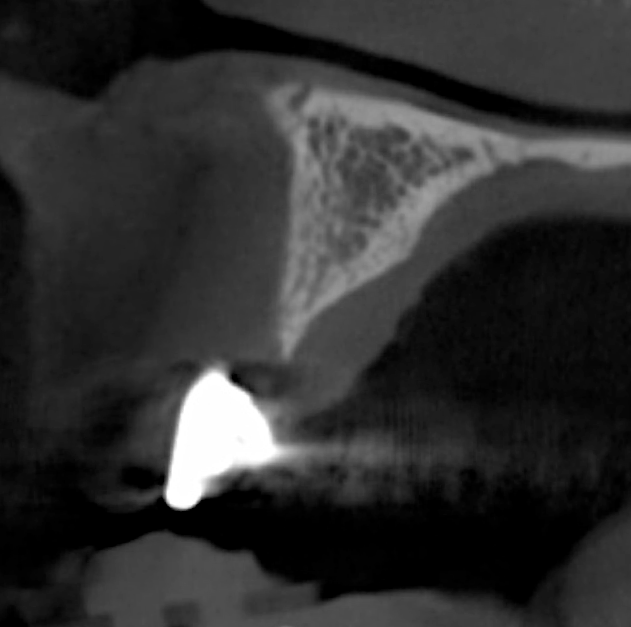

Tomographic images revealed a large tridimensional defect, with vertical and horizontal loss of bone extending to the apical third of teeth Nos. 6 and 8. Additionally, a buccal bone dehiscence was evident on tooth No. 5, and thin labial plates secondary to the orthodontic movement were present in several areas (Figure 3 and Figure 4).